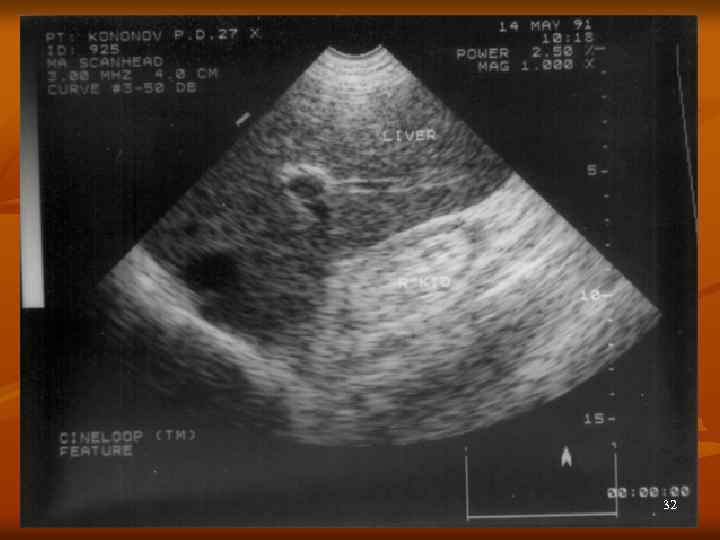

Диагностика ХГН n n n Общий осмотр – или норма, или от facies nephritica до анасарки Общий анализ мочи Кровь - анемия, повышение креатинина и мочевины УЗИ, КТ, МРТ – обнаружение уменьшенных в размерах почек Как причина вторичной гипертензии 29

32